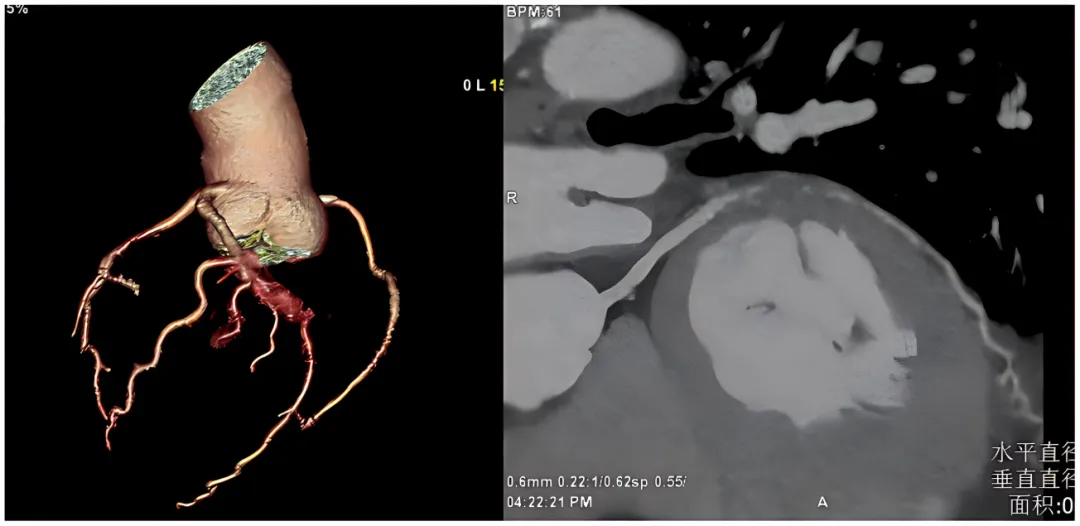

我立刻换到另一台需要人工后处理的设备,重新手动重建血管。

人工处理图像

结论明确:左回旋支中段,完全闭塞。

我把高师傅和小伙子叫到办公室,把图像指给他们看。

“这根血管,已经堵死了。”我指着屏幕上那个黑色的缺口。